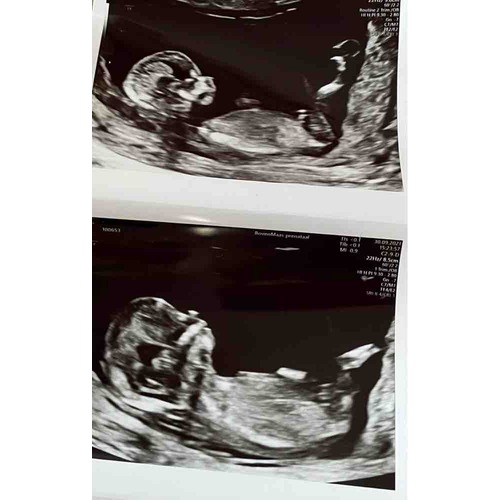

Onder de beentjes lijkt beetje opgezwollen.. precies 2 tegen elkaar bij een jongetje zie je een balletje eronder dan

Daar zie je precies een piemeltje en een balletje, is mijn echo, weet ook nog niet 100% zeker maar dat maken ze mij wijs Hahaha 😅🙈

Staat inderdaad ook omhoog, dus een jongen!

Echt overduidelijk een jongen hoor haha! Onwijs leukkk❤️😍